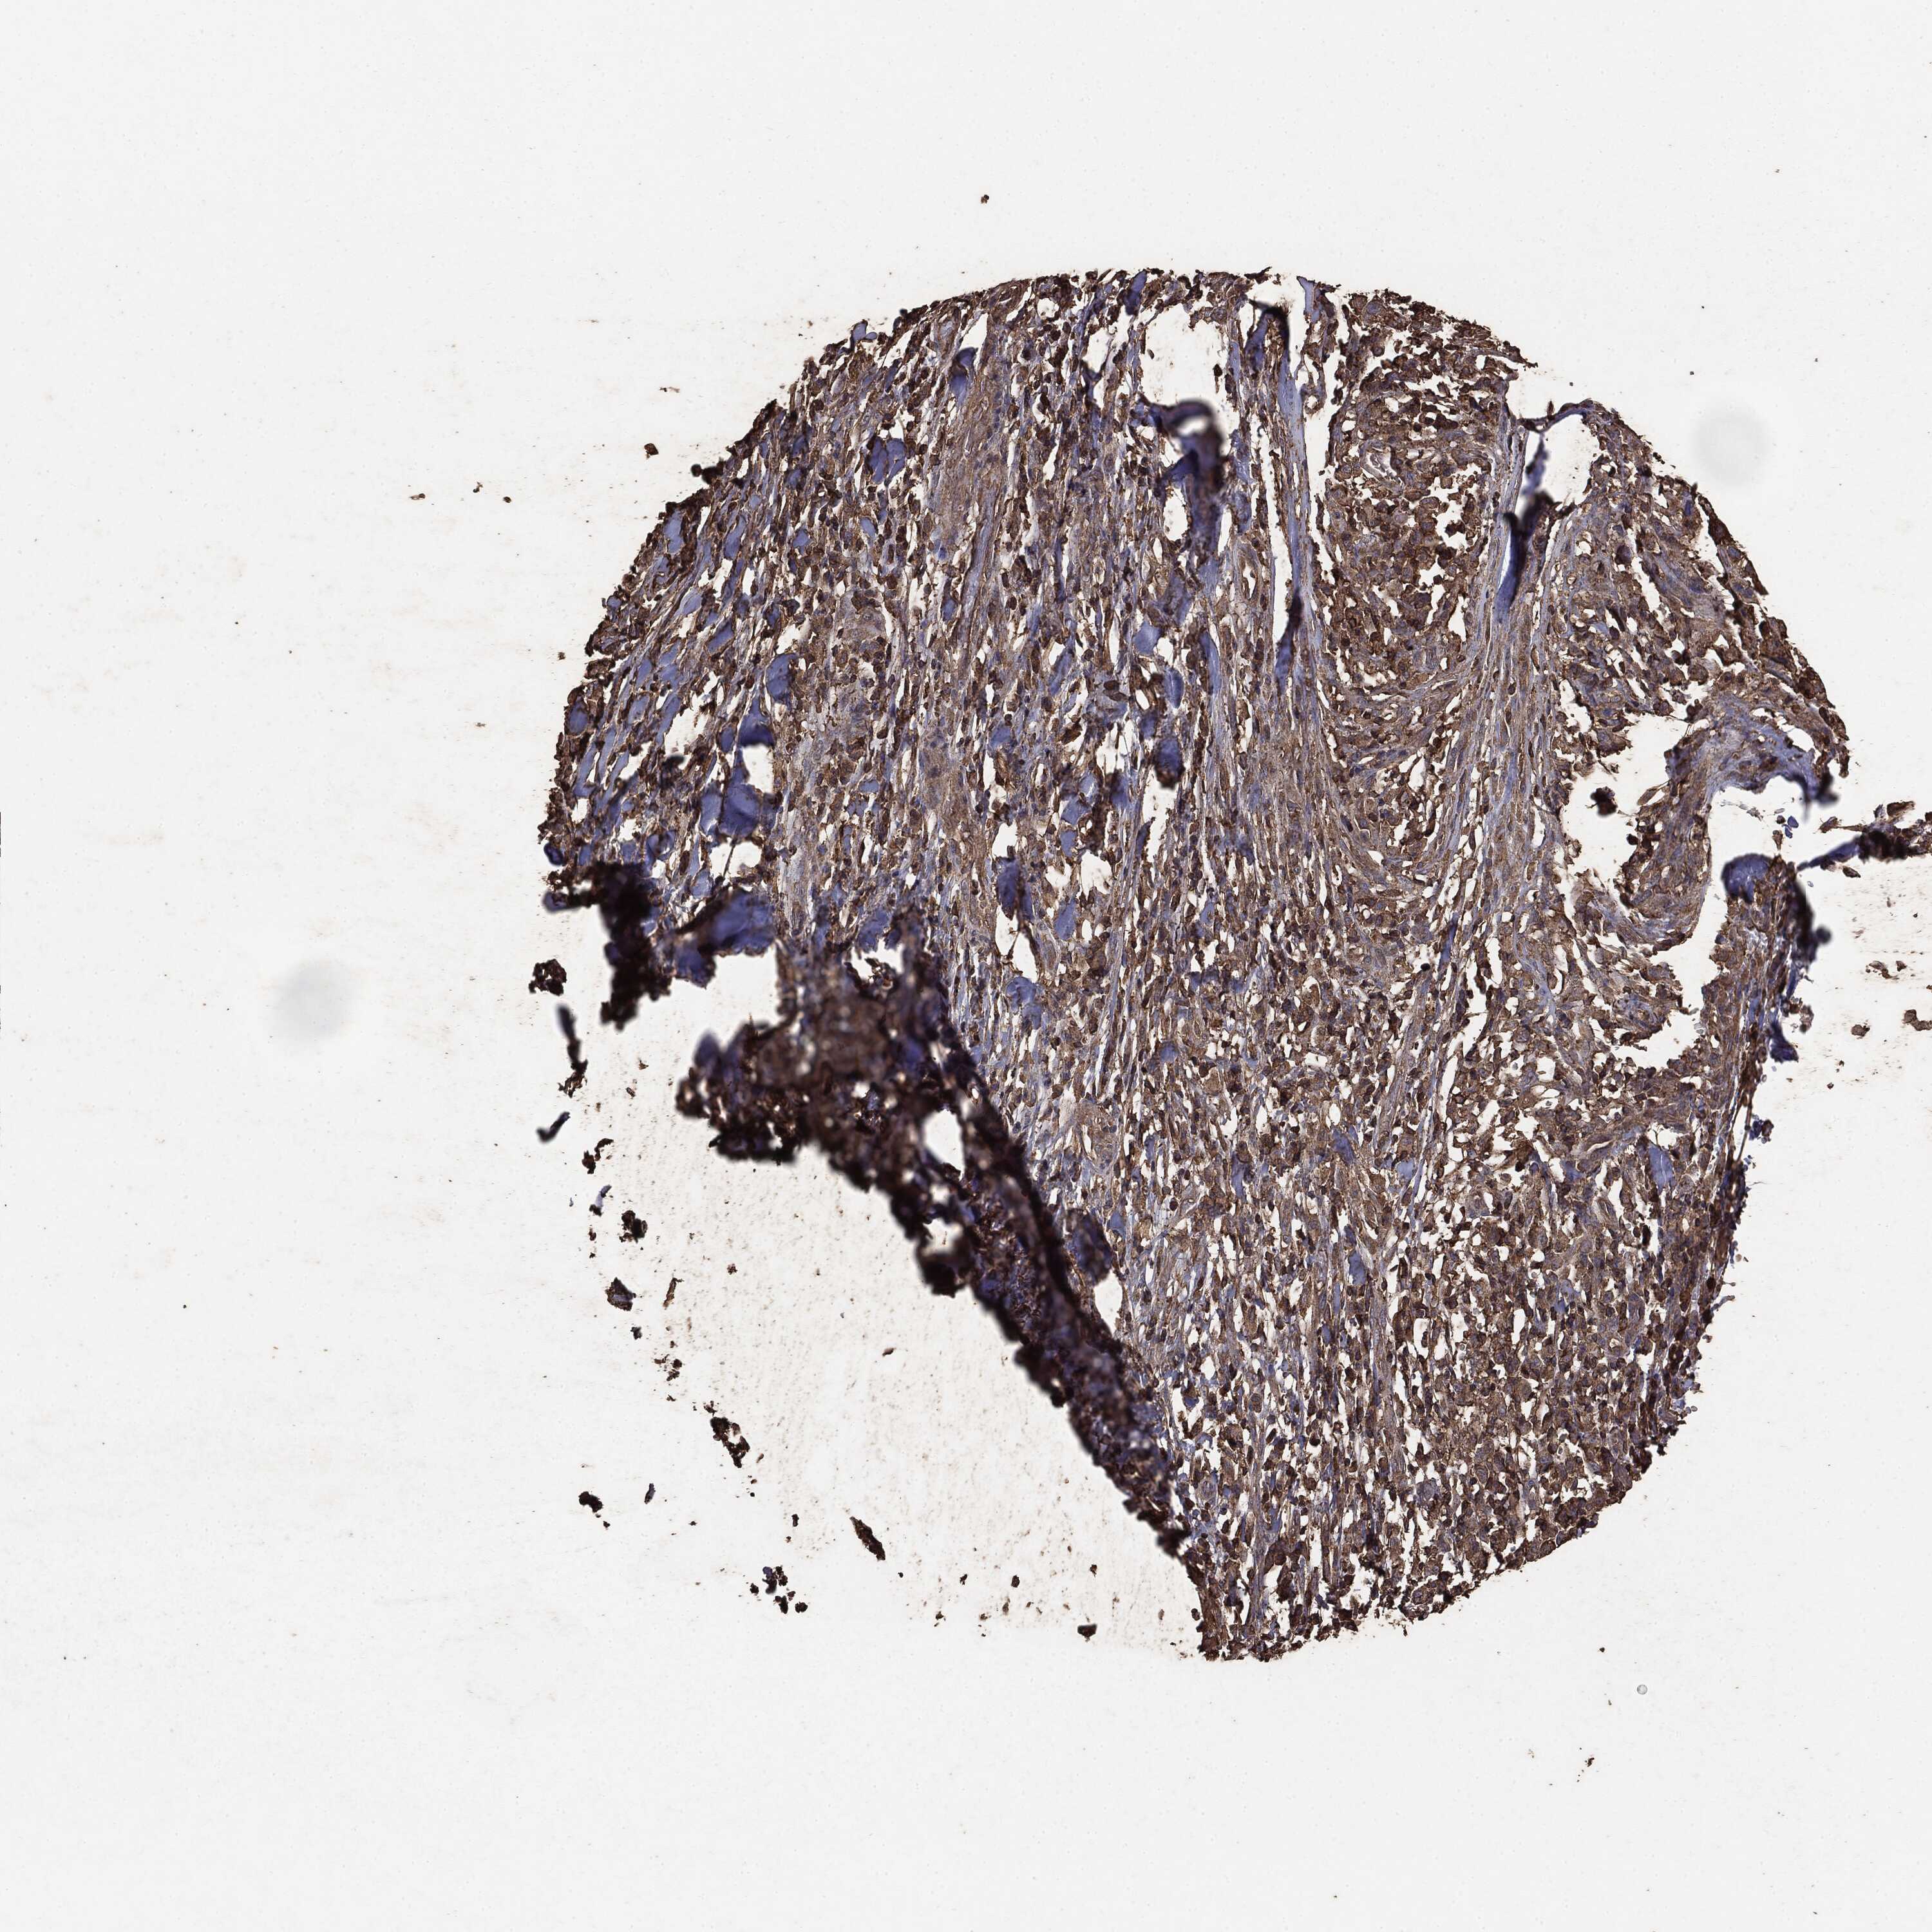

MELANOMA - Protein expressioni

A mouse-over function shows sample information and annotation data. Click on an image to view it in a full screen mode. Samples can be filtered based on level of antibody staining by selecting one or several of the following categories: high, medium, low and not detected. The assay and annotation is described here.

Note that samples used for immunohistochemistry by the Human Protein Atlas do not correspond to samples in the TCGA dataset.

Antibody stainingi

Antibody staining in the annotated cell types in the current human tissue is reported as not detected, low, medium, or high, based on conventional immunohistochemistry profiling in selected tissues. This score is based on the combination of the staining intensity and fraction of stained cells.

Each image is clickable and will lead to virtual microscopy that enables deeper exploration of all samples and also displays staining intensity scores, fraction scores and subcellular localization as well as patient and tissue information for each sample.

CAB069425

CAB080053

CAB080065

CAB080070

CAB080081

CAB080095

CAB080097

Staining

High

Medium

Low

Not detected

Intensity

Strong

Moderate

Weak

Negative

Quantity

>75%

75%-25%

<25%

None

Location

Nuclear

Cytoplasmic/membranous

Cytoplasmic/membranous,nuclear

Malignant melanoma, NOS

Malignant melanoma, Metastatic site